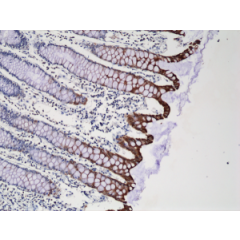

anti-Cytokeratin-20 (human), Rabbit Monoclonal (RM283)

anti-Cytokeratin-20 (human), Rabbit Monoclonal (RM283)

REV-31-1166-00 REV-31-1166-00-R100 100 µl CHF 468.00